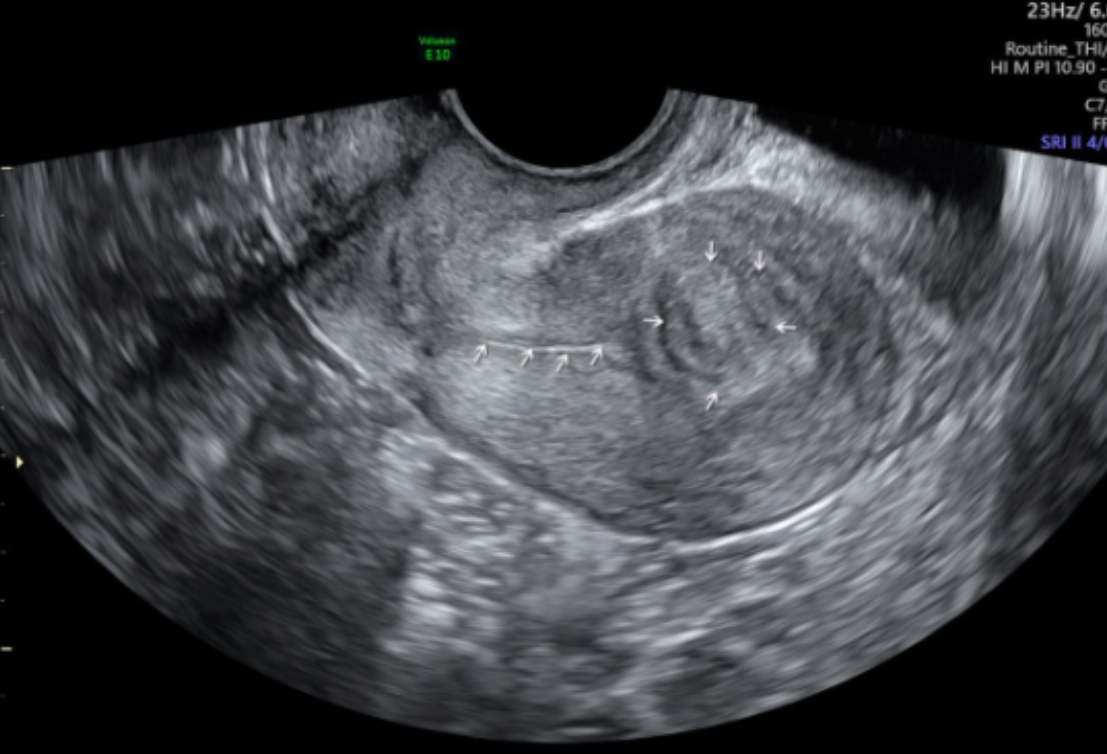

Name the type of fibroid and its location

Pedunculated

Anterior

Intramural

Posterior

Submucosal

Subserosal